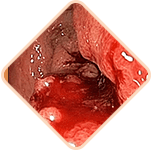

Sangrado durante la defecación

o rastros de sangre en las heces

Prolapso hemorroidal

Sensación de cuerpo extraño y

pesadez

Sensación de picor y

quemazón en el ano

Dolor al defecar,

caminar o sentarse

Sensibilidad al tacto de

los nódulos hemorroidales